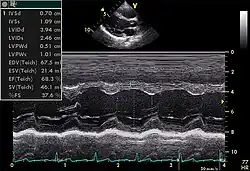

M-mode

Motion mode, though less commonly used, plays an important role in modern echocardiography. It has an advantage over 2D echocardiography due to its high temporal resolution (up to 1000 frames/sec). Examples of its use include accurate measurement of LV size, assessment for presence of cardiac tamponade, and assessment of RV function with TAPSE (tricuspid annular systolic plane excursion).

TTE utilizes one- ("M mode"), two-, and three-dimensional ultrasound (time is implicit and not included) from the different windows. These can be combined with pulse wave or continuous wave Doppler to visualize the velocity of blood flow and structure movements. Images can be enhanced with "contrast" that are typically some sort of micro bubble suspension that reflect the ultrasound waves.